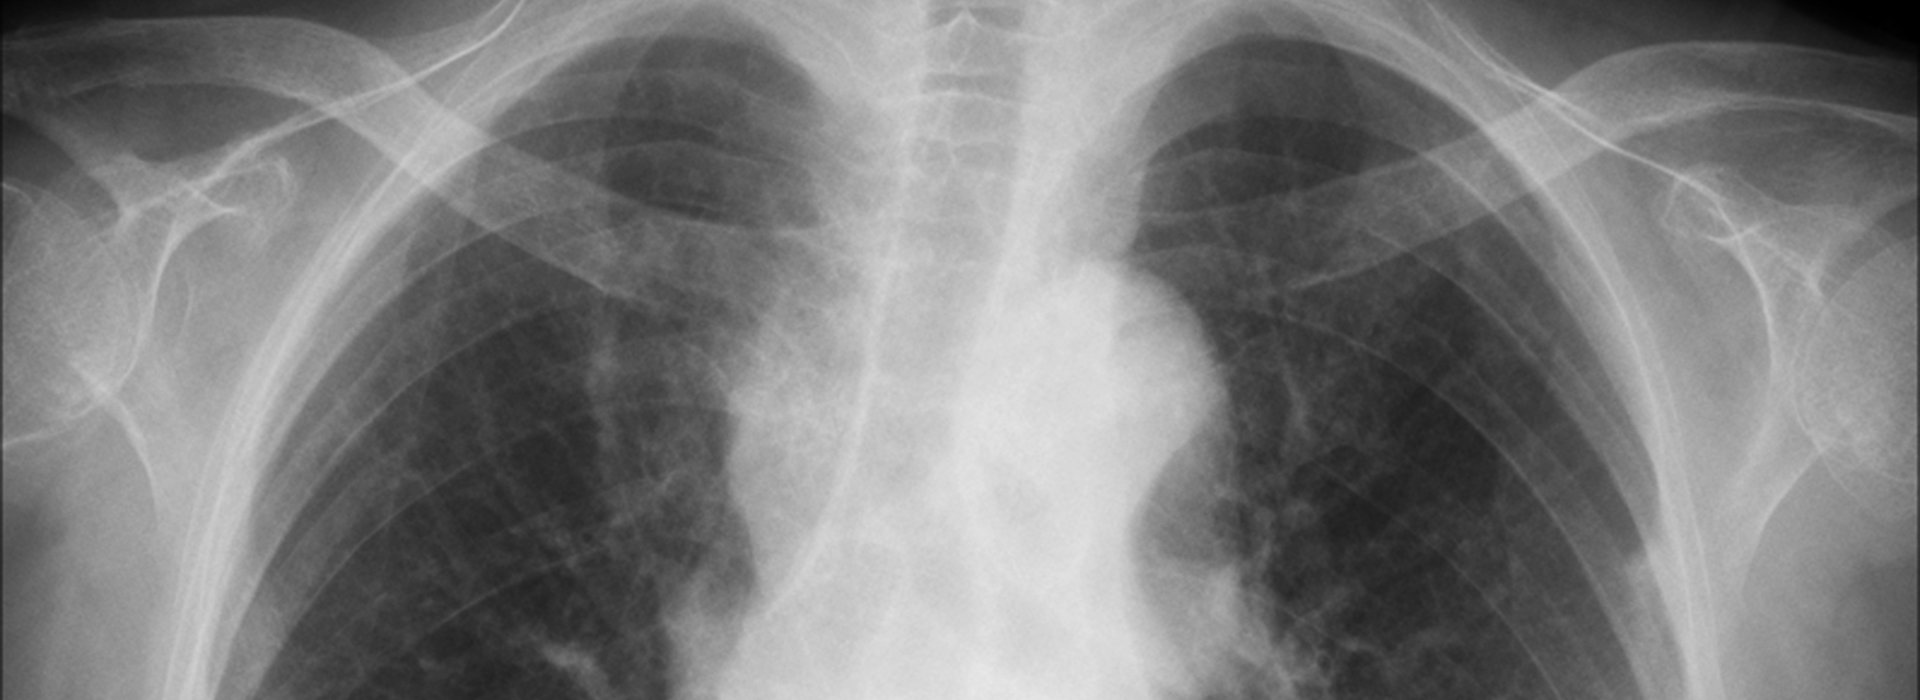

Η πολυετής επικοινωνία μας με, κλινικές, νοσοκομεία, ιατρούς και πελάτεςαπό όλο τον κόσμο, μας έχουν δώσει πολύτιμη εμπειρία και μοναδικό προβάδισμα στην τεχνογνωσία. Με την πάροδο των ετών, οι υπηρεσίες μας στην αντιγραφή και ψηφιοποίηση (scanning) ακτινογραφιών, μαγνητικής και αξονικής τομογραφίας, μαστογραφίας, σπινθηρογραφήματος, αγγειογραφίας, υπερηχοτομογραφίας και κάθε είδους ιατρικής εξέτασης που απεικονίζεται σε φιλμ, έχουν εξελιχθεί σύμφωνα με τις τεχνολογικές απαιτήσεις και συνεχώς εξελίσσονται για να διατηρούν το κορυφαίο επίπεδο ποιότητας και αξιοπιστίας.

- Αντιγραφή Ιατρικών Εξετάσεων

- Ψηφιοποίηση Ιατρικών Εξετάσεων

- Εκτύπωση Ιατρικών Εξετάσεων